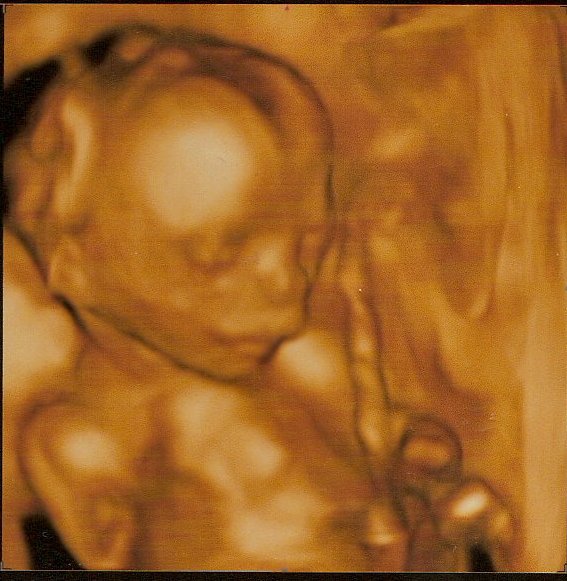

Jsem ve 20tt a zatím to vypadá dobře, ládovali mě těmi kortikoidy, abych zase nepotratila a vypadá to, že to snad pomohlo. Hodím ti sem jednu fotečku, jestli nevadí, je z 19. týdne. Teprve dnes jsem to přiznala v práci, pořád jsem čekala nějaký karambol. Snad to už bude dobré. Ingrid, to mě moc mrzí, že to zatím nevychází

Lucy nádherná fotka Bea už je tak daleko?TO není ani možné docela je škoda že ty holky ta partička už semka nechodí

Tobě mocinky gratuluji opravdu vypadá nádherně.A jak jinak v práci reagovali nevyptávali se moc?